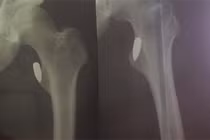

| Hình ảnh đầu đạn vẫn nằm trong đùi nạn nhân Lộc. |